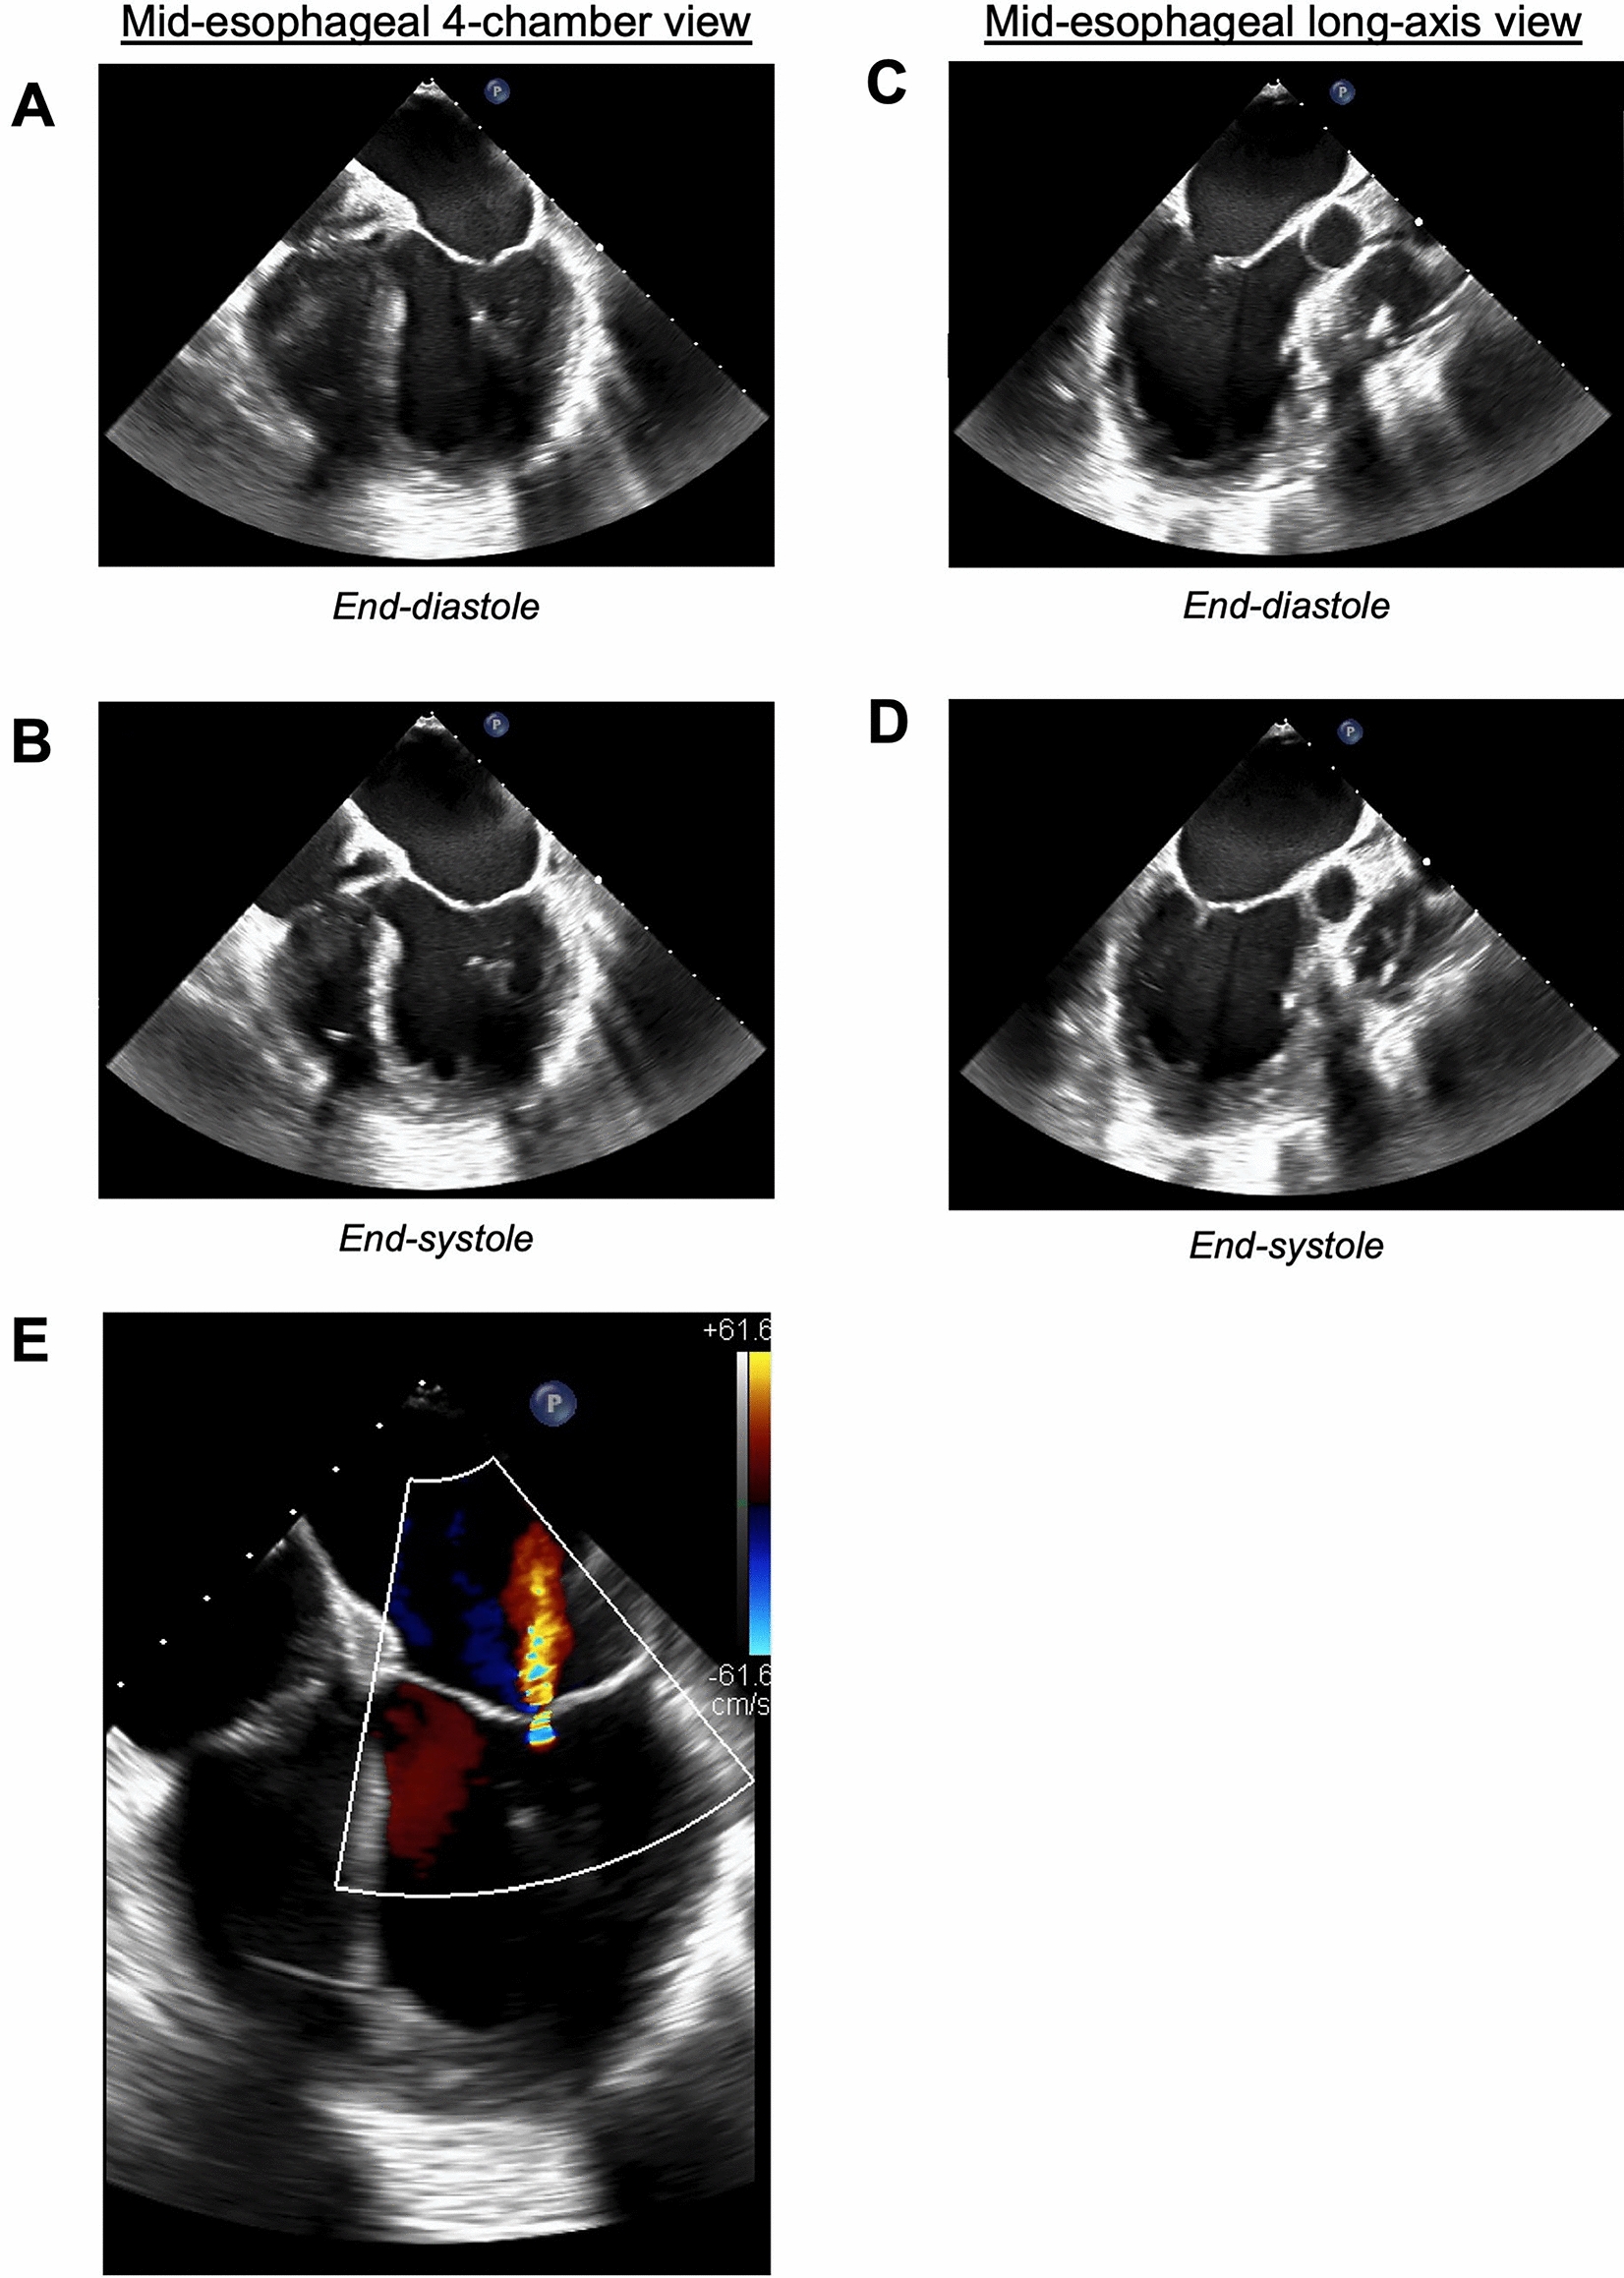

Fig. 2

Transesophageal echocardiogram obtained 25 min after the initial epinephrine bolus. Representative images from the mid-esophageal four-chamber view (transducer angle 0°) are shown at A end-diastole and B end-systole. Representative images from the mid-esophageal long-axis view (transducer angle 116°) are shown at C end-diastole and D end-systole. Significant contractility is observed only in the apical third of the left ventricle. The basal and mid-segments of the left ventricle appear nearly akinetic. The mid- and basal segments of the interventricular septum bow into the right ventricle. E Doppler imaging of the mitral valve showing a small, central regurgitant jet

A 54-year-old woman with May–Thurner syndrome complicated by multiple deep venous thromboses and chronic venous insufficiency, hypothyroidism, obesity, and generalized anxiety disorder presented for elective venous revascularization of the left lower extremity. For general anesthesia with elective intubation, the patient received midazolam, fentanyl, propofol, rocuronium, and sevoflurane, with cefazolin and bivalirudin administered for surgical prophylaxis and procedural anticoagulation, respectively. A low-dose phenylephrine infusion (10–30 mcg/min) was started to counteract vasodilation induced by the anesthetic agents. Immediately after pharmaco-mechanical thrombolysis with alteplase, the patient became acutely hypoxemic and then hypotensive to 56/30 mmHg. Peak inspiratory pressures increased from 21 to 28 cmH2O. The patient received a total of 1 mg epinephrine intravenously in three doses over 3 min (0.2 mg initially, 0.2 mg 2 min after the first dose, and 0.6 mg 1 min after the second dose), transiently increasing her blood pressure to 246/133 mmHg. She subsequently became hypotensive to 85/50 mmHg and was started on an epinephrine infusion and inhaled epoprostenol. The rate of the phenylephrine infusion was increased. An invasive pulmonary digital subtraction angiogram showed no pulmonary embolism to the level of the segmental pulmonary arteries. Pulmonary artery pressures were directly measured at ~65/45 mmHg via pulmonary artery catheterization. The electrocardiogram was remarkable for diffuse T-wave inversions and down-sloping ST-segment depressions, most marked in the anterior precordial leads (Fig. 1). Intraoperative transesophageal echocardiogram (TEE) showed an LVEF of 10–15%, global left ventricular hypokinesis with apical sparing, mild mitral regurgitation, and normal right ventricular systolic function (Fig. 2, Videos 1 and 2). The planned procedure was aborted.

Video 1: Mid-esophageal four-chamber view from the transesophageal echocardiogram obtained 25 min after the initial epinephrine bolus. Still images from this view are reproduced in Fig. 2A and 2B (MP4 28088 KB)

Video 2: Mid-esophageal long-axis view from the transesophageal echocardiogram obtained 25 min after the initial epinephrine bolus. Still images from this view are reproduced in Fig. 2C and 2D (MP4 29517 KB)